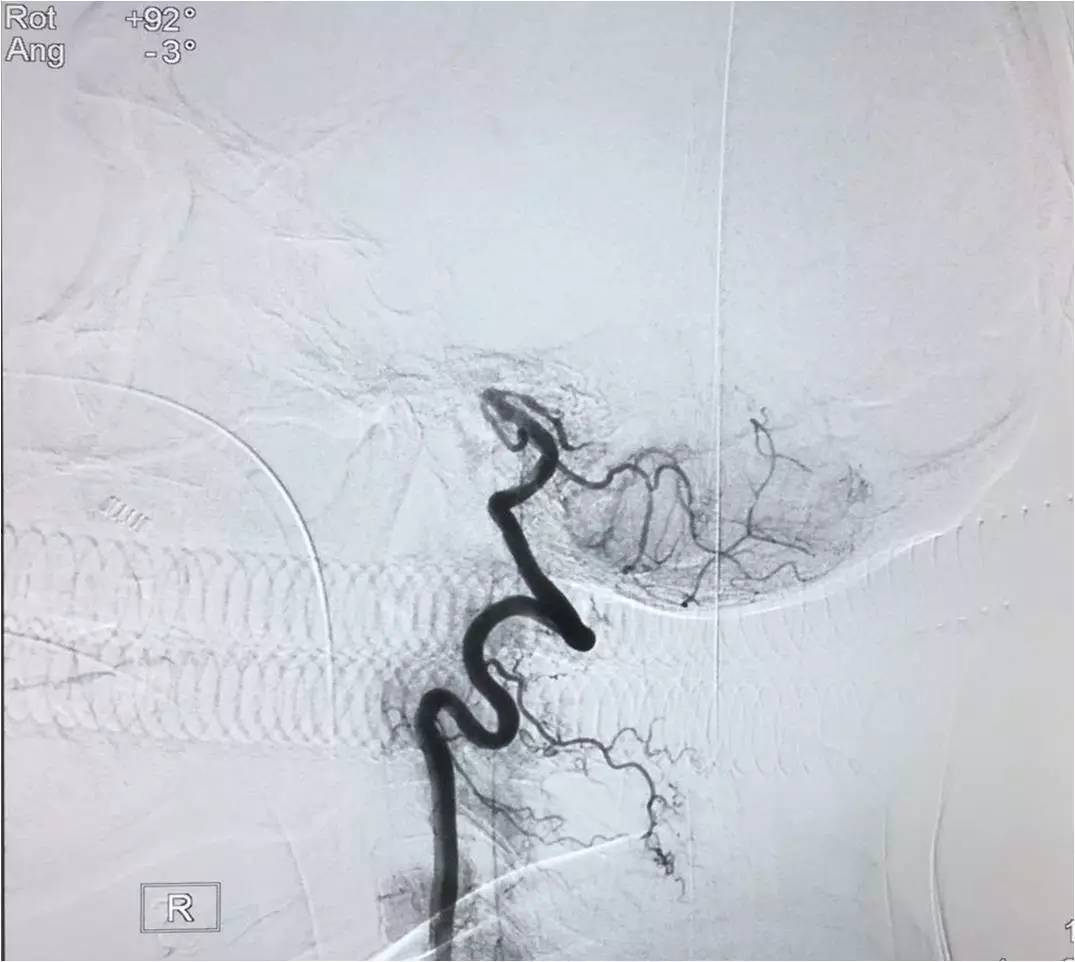

▼将Solitaire FR 送进微导管后将支架至于闭塞。部位远端,定位释放支架,保持原位5-10分钟后,将支架和微导管同时回撤。